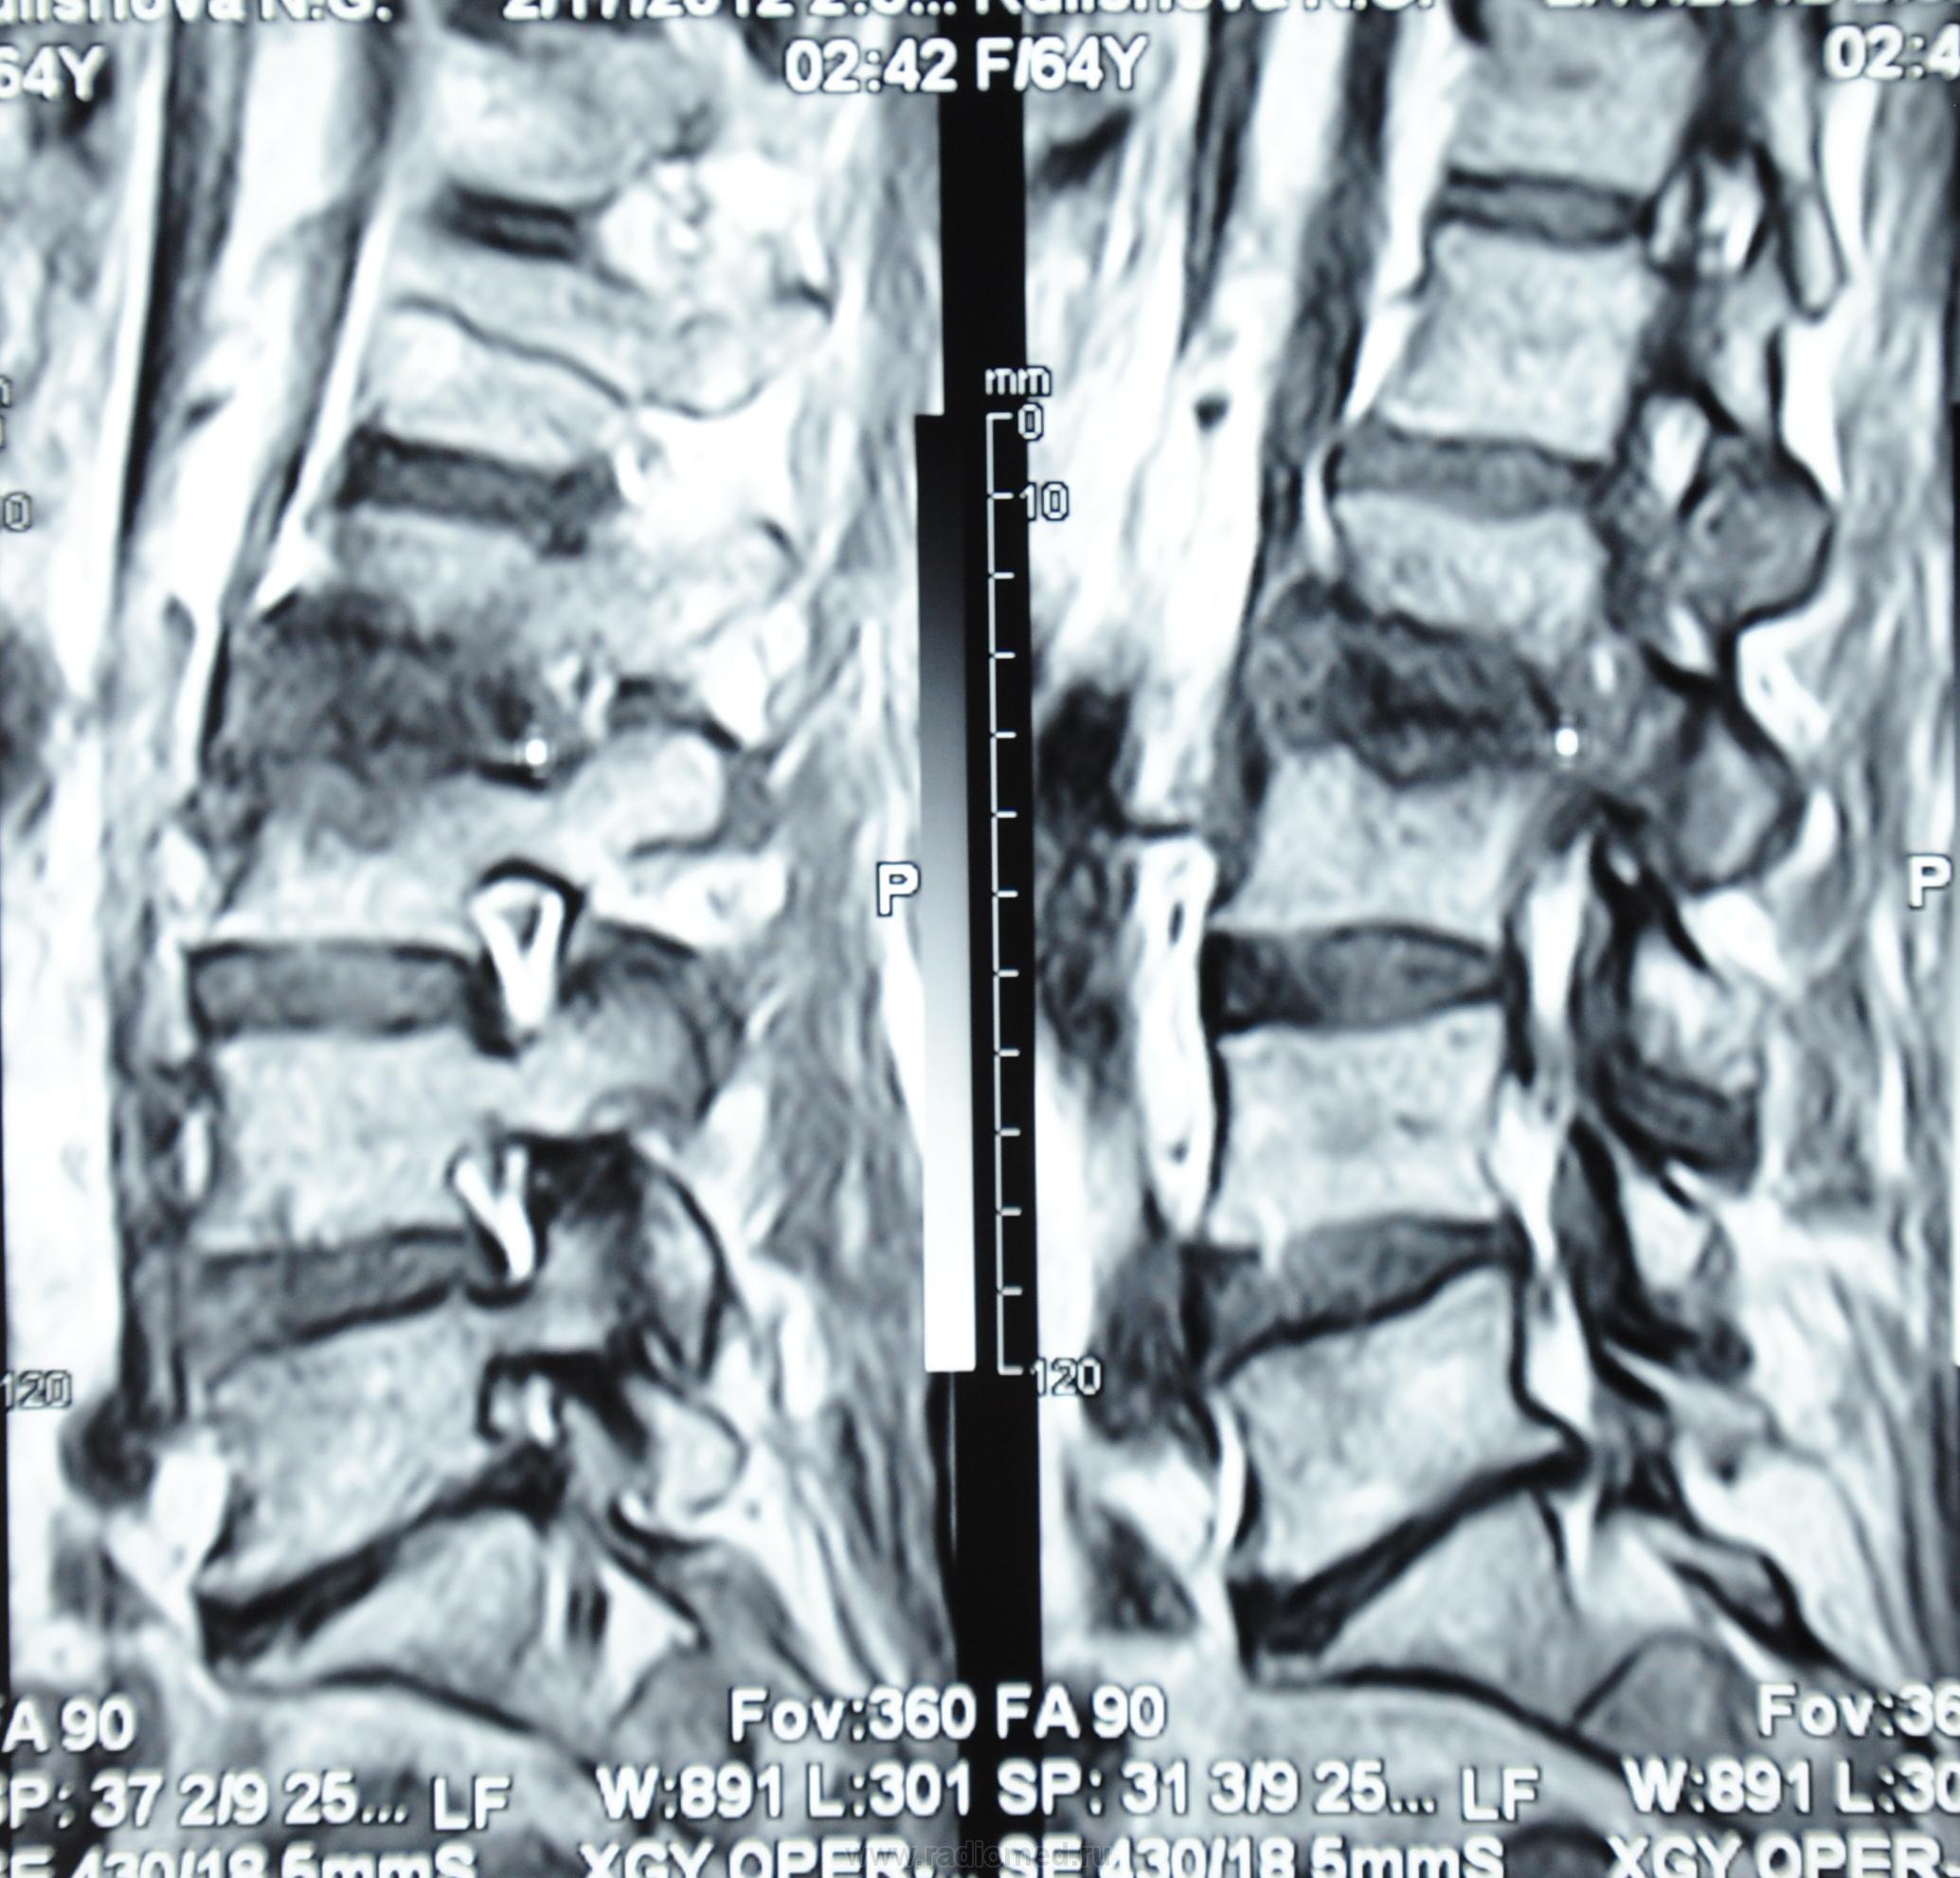

Мне видится здесь последствия зверского дисцита.  Предположу, ситуация не острая - данных за отек соответсвующих позвонков нет, хотя для убедительности нужен FatSat.  Из этого делаем вывод- на первое место исход воспаления, с формированием кистозных изменений, на второе - быть может нечто постравматическое с последующим, опять же, дисцитом.

При пункция патологического участка позвоночника - Лимфома позвоночника. Передан онкологам на лечение.

Уважаемый Николас, диагностировать лимфому по представленным сканам-высший пилотаж.Аксиалы, короналы напрочь отсутствуют-как можно обнаружить паравертебральный мягкотканный компонент ( если он имеет место быть, конечно)????.А вот явные признаки спондилодисцита имеются.

Уважаемые коллеги, по мне так МРТ-картина нетипична для лимфомы. Это не значит, что это не лимфома, но всё же не похоже, если проанализировать имеющиеся признаки.

По мне так спондилодисцит. Характерный жидкостной сигнал в диске, деструкция смежных позвонков. А уж какой этиологии, это пусть клиницисты решают.